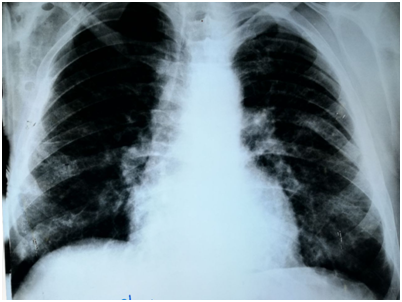

The patient's labs level was within normal except for CRP was elevated. By three separated measurement (one hour between each), water deprivation test revealed increased serum osmolality, increased serum Na+ and decreased urine osmolality. Hormonal Laboratory tests showed decreased FT4 and Testosterone. Magnet Resonance Imaging of pituitary gland was normal and no abnormality was detected (Figure 1). Chest X-ray showed diffuse interstitial reticular densities in both pulmonary fields (Figure 2). X-ray of pelvis and legs showed lytic lesions.

Pulmonary involvement is observed in 20-40% of LCH patients and can give symptoms, such as pneumothorax, dyspnea, tachypnea, and cough. Imaging studies of the lungs may reveal cysts and micronodular infiltrates.7 The patient had grade II dyspnea. CXR and MS- CT imaging of the lungs showed diffused interstitial reticular density. We performed Bronchoscopy and biopsy that showed histological features consistent with LCH.